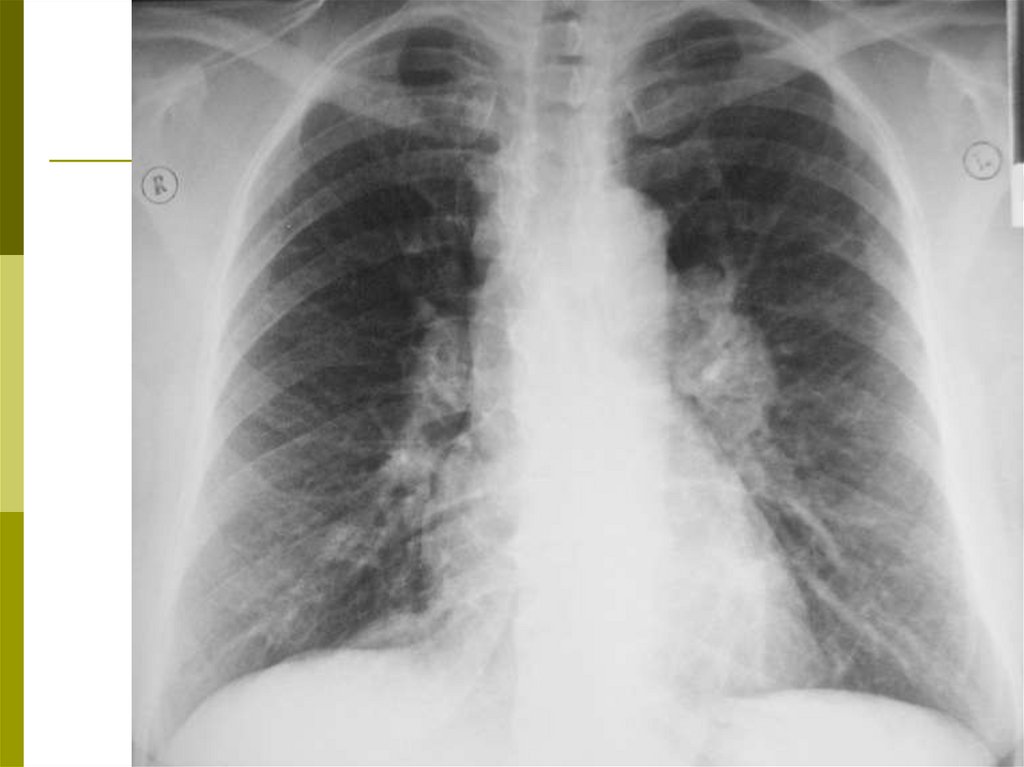

Рентгенография

В острой фазе – изменений можно и не заметить.

При подостром течении - мелкие (милиарные)

очаговые тени, преимущественно в средних полях

на фоне понижения прозрачности лёгочной ткани

– симптом «матового стекла». Реже –

множественные инфильтративные облаковидные

или более плотные тени с обратным развитием в

течение недель и месяцев.

В хронической стадии выявляются признаки

диффузного фиброза – крупная ячеестость

лёгочного рисунка («сотовое лёгкое»)